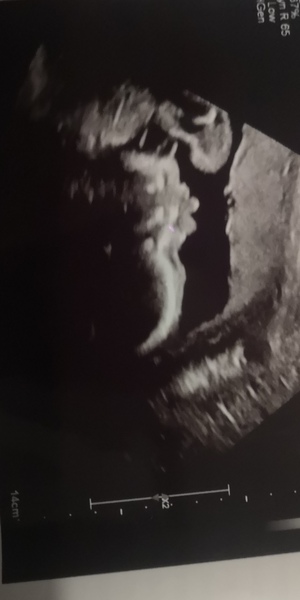

Knotemma · 01/07/2020 14:32

All went well for the growth scan, got to see the consultant and she's happy for me to remain midwife led because everything is still looking good. Goblin is a whopping 2lb10 and bang on 50th percentile, which is a relief because DH was a massive baby! Back for a second growth/reassurance scan in 6 weeks. I'm pretty sure little one was sticking their tongue out for the camera!

Lovely scan picture there!

That’s excellent that everything is looking good with your little goblin @Knotemma

Great scan news @knotemma and @footprintsintheslow! And a really lovely scan picture. It's always great to hear good news.

@Knotemma what an amazing scan, I can see the face so clearly! I think you're right - so cute with the tongue poking out!